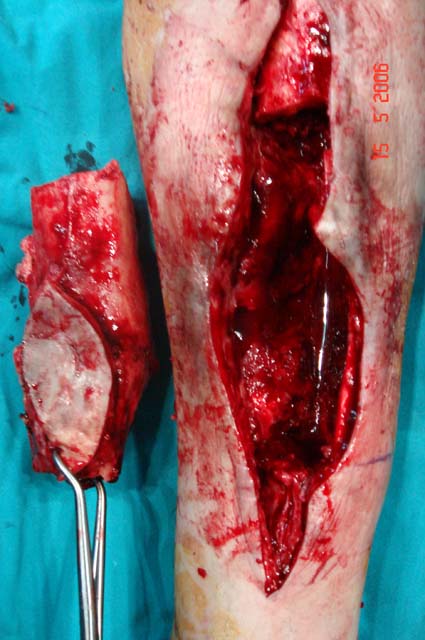

Kronik osteomiyelit, kemik ve yumuşak dokularda nekroza yol açar. Ölü kemik, patojen mikroorganizmalara ev sahipliği yapan bir nidus oluşturur. Konağın savunma sistemleri, mikroorganizmalarla baş etmek için sıklıkla optimal koşullarda değildir. Dolaşım bozukluğu yüzünden enfeksiyon bölgesine antibiyotikler yeterince ulaşamaz. Bu nedenle ölü dokuların ortamdan tamamen uzaklaştırılması gerekir (radikal debridman).

Uygun radikal debridman tüm nekrotik kemik ve yumuşak dokuların çıkartılmasını gerektirir, ve sıklıkla uzuvda instabiliteye neden olur. Kalan kemik ve yumuşak doku defektinin bir şekilde fiksasyonu ve rekonstrüksiyonu gereklidir. İlizarov’un ortaya koyduğu distraksiyon osteogenezi yöntemi, kaynamanın elde edilmesi, deformitenin düzeltilmesi, bacak boy eşitsizliğinin giderilmesi ve segmental defektlerin rekonstrükte edilmesi için başarıyla kullanılmaktadır.